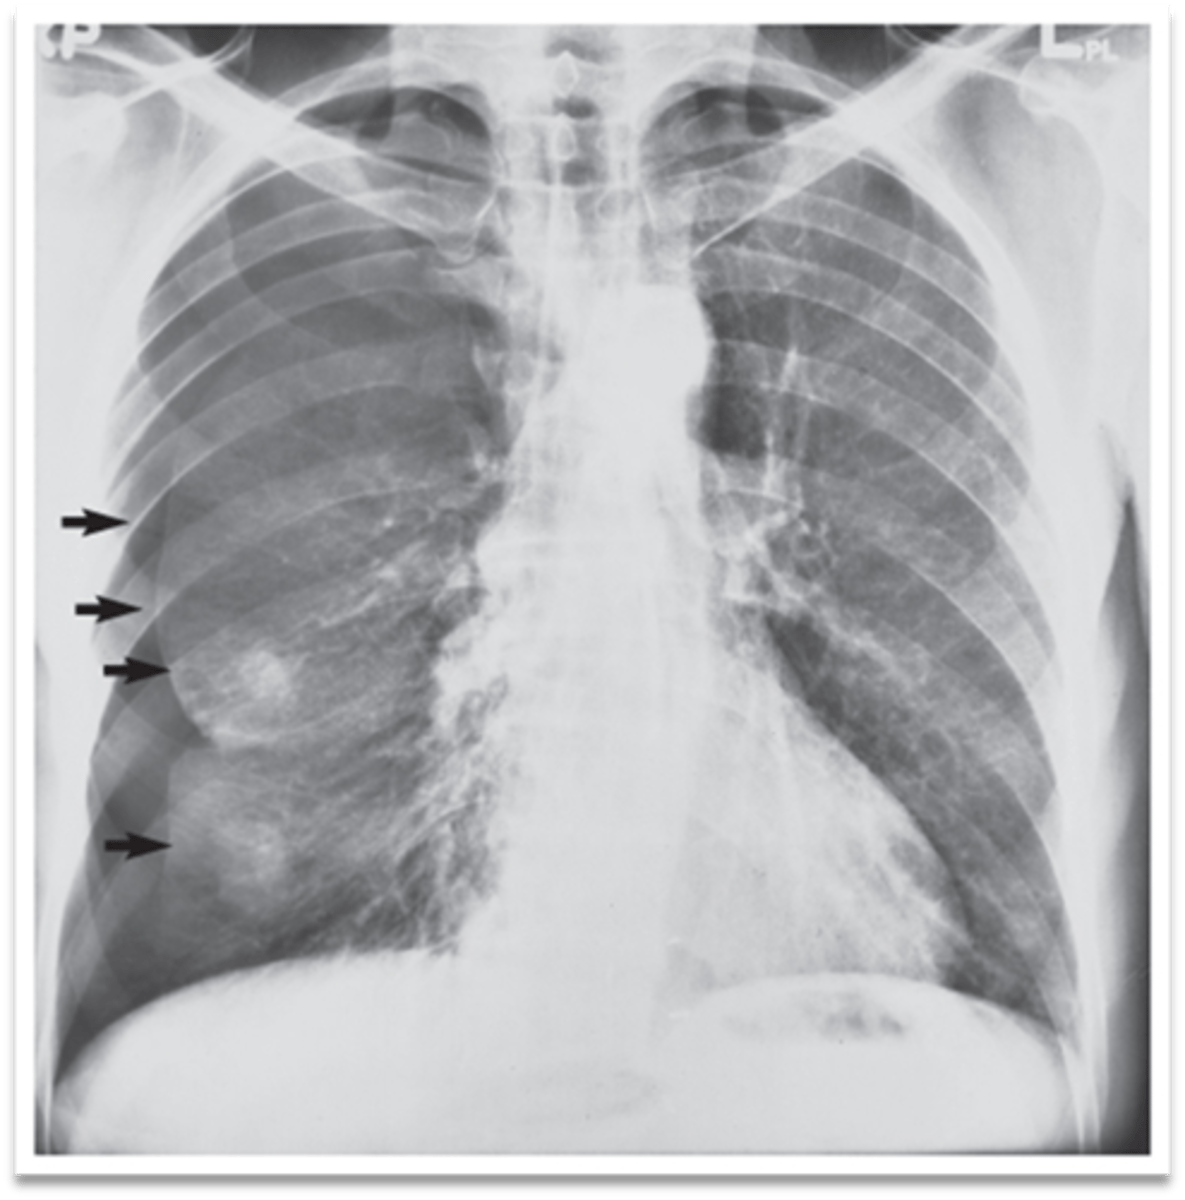

Possible CHF (presence of Kerley B lines)

What does the chest film show?

CHF (Kerley B lines- short, horizontal white lines that indicate fluid accumulation)

Interpretation?